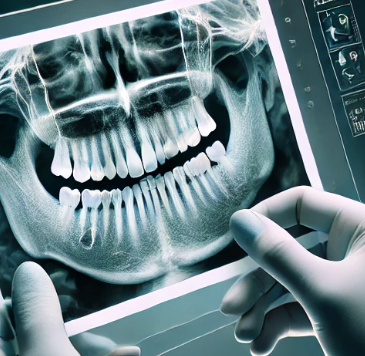

어금니 임플란트를 시작하기 전에, 정확한 진단이 필수입니다. 치과 전문의는 X-레이, CT 스캔 등을 통해 환자의 구강 상태를 분석하고, 어금니 뿌리와 잇몸 상태를 확인합니다. 또한, 환자의 뼈 상태를 확인하여 뼈 이식이 필요한지 여부를 판단합니다. 이 진단 과정이 끝나면 개별 환자에게 맞는 시술 계획을 수립하게 됩니다.